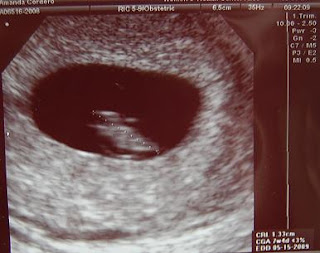

Okay so last night was horrific, I kept waking up with terrible stomach cramping on and off all night. This morning I woke up feeling like a zombie and was super nauseous, so I finally called in sick for the first time and they told me to go ahead and come in for an appointment (I hate sounding like a baby crier). So I came in and I took my mom with me and they said that it could be that it's getting worse so Dr. Barnes had me go in for an ultrasound to make sure the baby was okay first. The baby has grown so much in just 4 days, and guess what? The heart rate went up to 130 today. My mother joked around about how the baby looked like Patrick Star from Spongebob Squarepants *lol* Now the measurements say baby is 7 weeks and 4 days! We should get an accurate measurement in 2 more weeks.